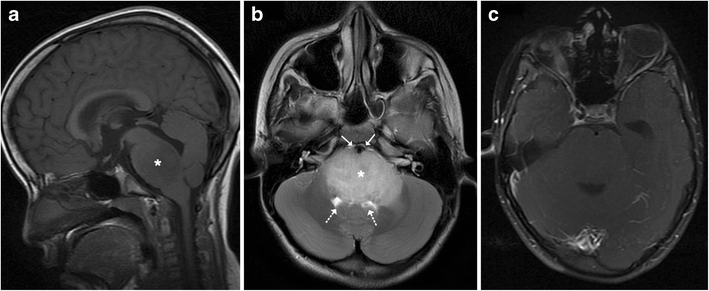

MRI images obtained on admission. (A) Sagittal T1-weighted ...

MRI images obtained on admission. (A) Sagittal T1-weighted ... from www.researchgate.net

Mass lesions in the brainstem cause severe alterations in the level of consciousness (such as coma). See more of brain stem on facebook. Axial t2 flair mri image showing a mass in the brainstem consistent with brainstem glioma.